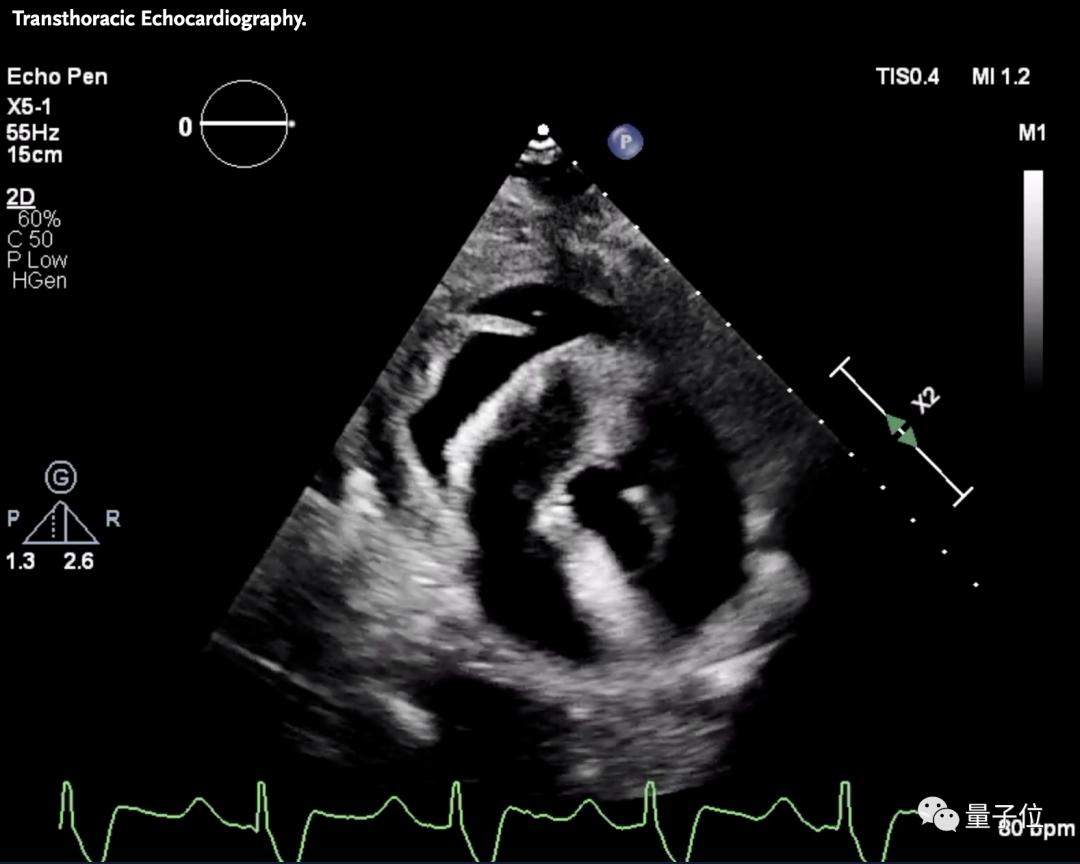

此前曾经有研究人员将经基因编辑的猪心脏移植给需要靠ECMO维持生命的心脏疾病患者的案例,该患者在接受移植的前49天没有任何异常,然后突然出现异常,在第60天因移植器官衰竭去世。

△